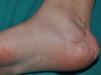

Subcutaneous neurofibromas, which we generally class as plexiform neurofibromas because they are usually associated with this histological pattern,43 can be predominantly diffuse or nodular on palpation. The diffuse lesions are manifest as subcutaneous masses of greater or lesser extension, with poorly defined borders and elastic consistency. Nodular subcutaneous neurofibromas consist of nodular lesions of rubbery consistency that follow the peripheral nerve tracts. On palpation, linear and beaded lesions with a firm consistency are apparent.7 They can appear anywhere on the body, but they are particularly common on the cephalic pole and neck, where they can be confused with swollen lymph nodes in their early phases (Fig. 9).